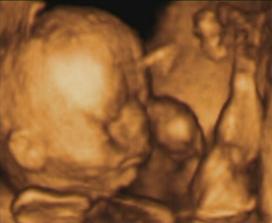

Moj prvy pokladik